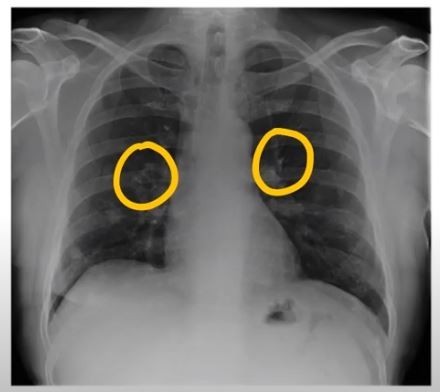

폐렴 증상 폐렴 치료

폐렴 증상을 겪는 그럴 경우 X선 촬영 및 배양 검사로 진단할 수 있어요. 필요에 따라 소변, 혈액, 혈청 검사, CT 등을 추가로 실시해요. 폐렴 진단을 받은 환자는 일반적으로 입원을 권장하지 않지만 젊거나 기초질병이나 호흡곤란이 심한 그럴 경우, 고령, 임신 등의 그럴 경우 전문기관에 방문해서 상황에 맞는 신속한 치료와 상태 개선, 위험예방을 받는 것이 좋아요. 폐렴 증상의 치료에서 가장 주요한 것은 항생제로 원인균을 제거하는 것인데요. 세균이나 바이러스 감염에 의해 발생하며 처음에는 항바이러스제를 통해 감기처럼 치료하기도 해요.